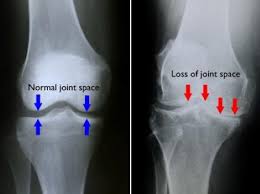

Osteoarthritis is the most common type of knee arthritis, affecting over 14 million Americans. It occurs when protective cartilage in the joint gradually wears down over time, allowing painful bone-on-bone friction.

OA can be primary (idiopathic) with no known cause, or secondary due to injury, obesity, overuse, or other joint stressors. As cartilage erodes, movement becomes stiff and painful. Fluid-filled cysts and bony growths may also develop around the joint.